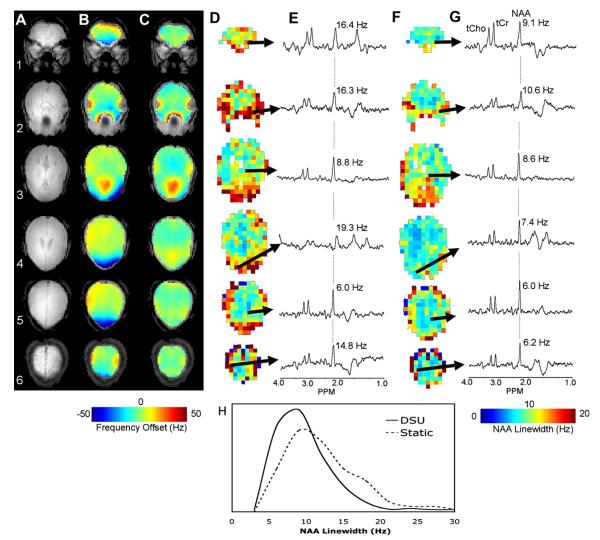

In conjunction with the measured B0 maps, DSU improvement is here quantified using the linewidth of N-acetyl aspartate (NAA), which was measured for all viable spectra in the presented data series.

Fig. 14 shows MRSI spectral improvements enabled through DSU. MRSI were acquired from 1-cm-thick axial slices ranging from the hippocampus to the top of the brain. A data matrix of 24 × 24 voxels over 24 × 24 cm was collected from each slice. The imaging sequence consisted of a slice-selective adiabatic inversion pulse followed by a 240-ms delay allowing for T1-nulled lipid suppression [70]. During this delay, water was suppressed by Gaussian-pulsed CHESS. Localization was accomplished with a slice-selective SLR-90 pulse and a pair of hyperbolic secant slice-selective adiabatic refocusing pulses followed by two-dimensional phase encoding gradients. Spectra were acquired with TE = 80 ms and TR = 3 s [62]. No additional outer volume suppression was used. Crushing gradients were applied before and after the refocusing pulses as well as between slices to suppress unwanted coherences.

Fig. 14.

(A) Anatomic images of MRSI slices, (B) B0 maps without DSU, (C) with DSU, (D) NAA linewidths across viable MRSI voxels with DSU, (F) without DSU, (E) spectra from indicated voxels without DSU, and (G) with DSU. (H) Provides a histogram of viable NAA linewidths across all slices with and without DSU. Images obtained at B0 = 4T. Reproduced from [62] with permission of Wiley-Liss, Inc., a subsidiary of John Wiley and Sons, Inc.

Field maps without (B) and with (C) DSU over the slice-specific ROIs utilized in shim optimization demonstrate the homogeneity improvements gained with slice-specific shim settings. [62] The impact of this homogenization on spectral quality is twofold. First, MRSI voxels distributed across slices will have reduced frequency variation, which improves water suppression. Second, narrowing of spectral linewidths will further improve water suppression and dramatically improve spectral quantification. The field maps (B–C) illuminate the former consideration, while N-acetyl-acetate linewidths without (D) and with (F) DSU quantify the latter. Selected spectra from the indicated voxels without (E) and with (G) DSU qualitatively show the overall improvement in spectral quality. Spectra are presented to demonstrate a wide range of improvements. The selected spectrum from slice 1 (in the periphery of the brain) shows tremendous improvement using DSU. Spectra from slice 4 (again near the periphery of the brain) demonstrate the improvements typical of DSU implementation. Finally, the spectra from slice 5 (in the middle of the brain, near the static-shim optimization volume) show negligible improvements using DSU. The advantages of DSU are plainly obvious. Qualitative improvements in the outer regions of the brain are presented in the selected spectra from slices 1 and 4. As seen in the B0 and NAA maps, DSU is able to dramatically reduce frequency variation and linewidths across most slices. The exception is slice 3, which is in the direct vicinity of both the auditory and sinus cavities. Due to the high-order of spatial inhomogeneity in this slice, a second-order slice specific shim setting is unable to improve significantly on the global static shim. However, this slice is an extreme case and significant improvements are made in all other slices.